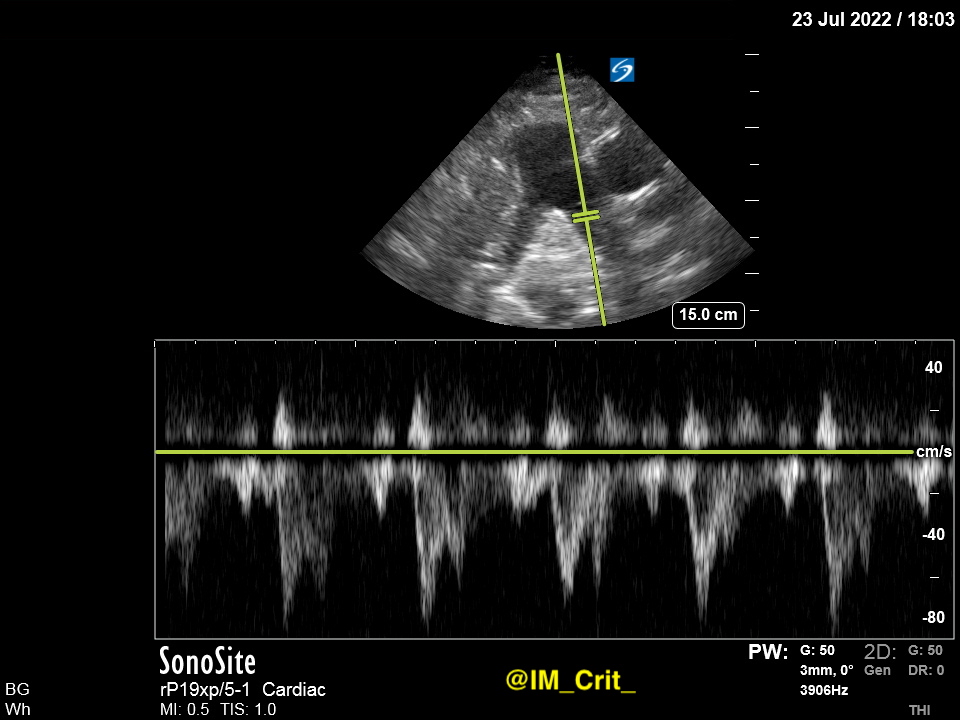

It is not always as clear as in this case but, if it is, you can interrogate w color Doppler and PW/CW separately each one of the PA branches (R - L):

PW Doppler in one side:

Sometimes you can see different PW profiles in the 2 branches... 👇 👇

PW Doppler focusing on the other side:

How is this 👆Doppler profile of the PA artery called? @khaycock2 has a great talk on this